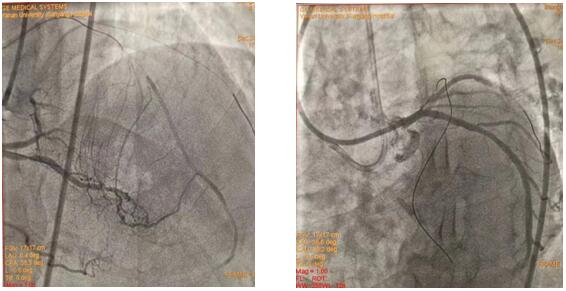

(插图说明:图1为双侧造影图、图2为导丝正向通过图、图3为求那边、图3为球囊通过图、图4为导丝逆向通过图)

在吴栋梁院长的协调安排下,从12月24日清晨7:30到12月25日清晨7:50安全完成62例介入手术。其中,心血管内科二病区介入团队在左梅主任的带领下,清晨七点半开始,C3830电极对于左束支区域起搏、永久起搏器的成功置入,逆向技术开通LAD近段无残端闭塞病变的顺利完成,创造着一个个生命的奇迹,为心血管病患者带来一个不平凡的平安夜。